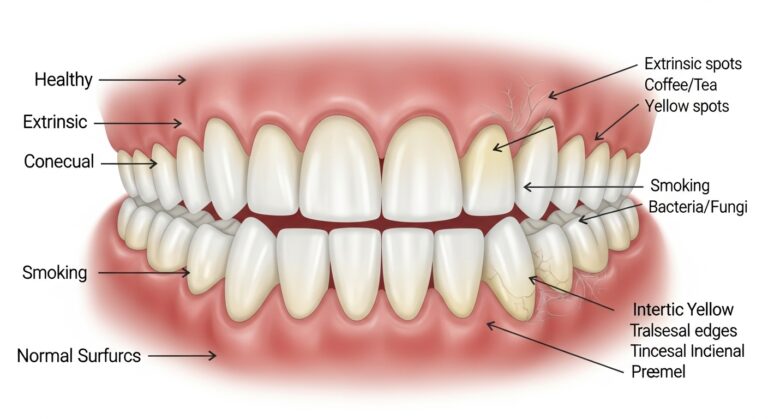

What Is It? Tooth discoloration may be caused by superficial stains or by changes in the underlying tooth material. Dentists divide…